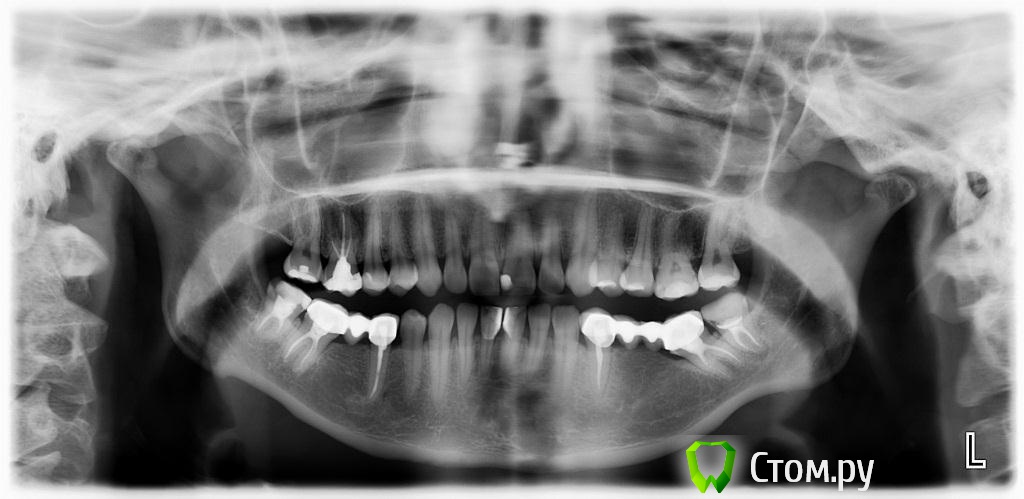

zzkz Опубликовано 6 марта, 2014 Поделиться Опубликовано 6 марта, 2014 Пациент 32 лет от роду. Известная особа в шоу бизнесе.С полостью рта не айс.Помогите разобраться и составить план лечения. Без лица(фото не делал) Жалобы на дискомфорт, трудность пережевывания пищи, с ее слов - как будто левая сторона не достает, в общем испытывает не удобства одни. На эстетику как ни странно ноль внимания. ВНЧС слева легкий щелчок при открывании/закрывании. Мышцы в норме. Но в фас и профиль подбородочная складка довольна выражена, как характерно при 2-ом классе. Фото моделей и панорама прилагаю Мой план пока таков:1. удаление 2-х восьмерок на н\ч2. каппа прозрачная, чтобы проверить реакцию ВНЧС при поднятии прикуса на пару месяцев3. снятие коронок4. воск5. импланты с аугментацией6. временное на металлопластмассе на имеющихся зубах7. через 4-5 мес. постоянные на имплантах как бы сделали Вы? Ссылка на комментарий

zzkz Опубликовано 7 марта, 2014 Автор Поделиться Опубликовано 7 марта, 2014 (изменено) апрайт 16,26? дистализация 37?(если это удасться) А что ей даст полноценная ортодонтия(инвизилайн или инкогнито)? Привести все в 1й класс? Как думаете если определить ЦС и от первых премоляров и дистальнее немного поднять прикус? Без большой ортодонтии. а так сказать полутотальчик, без фронта Изменено 7 марта, 2014 пользователем zzkz Ссылка на комментарий

Ayrat_zub Опубликовано 7 марта, 2014 Поделиться Опубликовано 7 марта, 2014 апрайт 16,26? дистализация 37?(если это удасться) А что ей даст полноценная ортодонтия(инвизилайн или инкогнито)? Привести все в 1й класс? Как думаете если определить ЦС и от первых премоляров и дистальнее немного поднять прикус? Без большой ортодонтии. а так сказать полутотальчик, без фронтау вас фронт компенсировался под нынешнюю высоту, выровняв молряы получите открытый прикус во фронте, с протрузией нижних резцов, нужно полноценно работать тут, для максимально функционально-эстетичного результата. Сделайте сет ап, пациентке нагляднее будет. Из телевизора она или нет, результат одинаково нужен) сделайте ТРГ, самому станет понятнее) Ссылка на комментарий

Bobby Опубликовано 7 марта, 2014 Поделиться Опубликовано 7 марта, 2014 (изменено) Сначала узнайте готова ли она проходить лечение не менее двух лет, не нарушая при этом график лечения? Мой скромный опыт подсказывает, что личение публичных людей не столь сложно с медицинской точки зрения, сколь с организационный (частые отмены визитов, капризы, не своевременная оплата оказанных услуг). Касаемо клинической ситуации. В идеале провести ортодонтическое лечение, чтобы изменить овербайт и оверджет. Увеличение вертикального расстояния окклюзии (высоты прикуса) у пациентов со 2-м классом (дистальный прикус) всегда переносится хуже и в случае не создания на керамике ретрузионной защиты, может приводить к дискомфорту и даже дисфункциям жевательного органа. Реставративное лечение требуется только в боковых участках? Каково состояние передних зубов?Нужно ТРГ. Изменено 7 марта, 2014 пользователем Bobby Ссылка на комментарий

zzkz Опубликовано 11 марта, 2014 Автор Поделиться Опубликовано 11 марта, 2014 И без расчетов взаимоотношение резцов будет видно Сагиттальная щель естьНаправлю на ТРГ. Что даст картина взаимоотношения резцов? Ссылка на комментарий